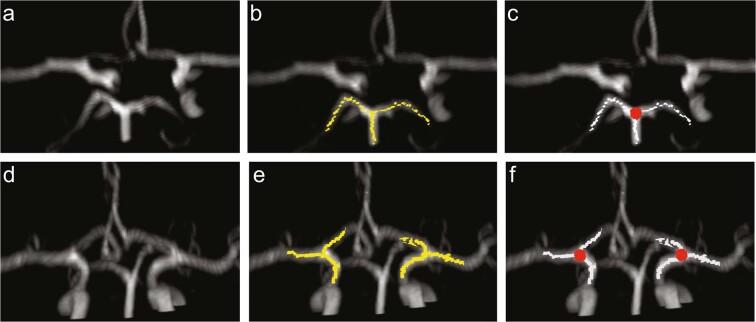

The arterial connections in the Circle of Willis are a central source of collateral blood flow and play an important role in pathologies such as stroke and mental illness. Analysis of the Circle of Willis and its variants can shed light on optimal methods of diagnosis, treatment planning, surgery, and quantification of outcomes. We developed an automated, standardized, objective, and high-throughput approach for categorizing and quantifying the Circle of Willis vascular anatomy using magnetic resonance angiography images. This automated algorithm for processing of MRA images isolates and automatically identifies key features of the cerebral vasculature such as branching of the internal intracranial internal carotid artery and the basilar artery. Subsequently, physical features of the segments of the anterior cerebral artery were acquired on a sample and intra-patient comparisons were made. We demonstrate the feasibility of using our approach to automatically classify important structures of the Circle of Willis and extract biomarkers from cerebrovasculature. Automated image analysis can provide clinically-relevant vascular features such as aplastic arteries, stenosis, aneurysms, and vessel caliper for endovascular procedures. The developed algorithm could facilitate clinical studies by supporting high-throughput automated analysis of the cerebral vasculature.